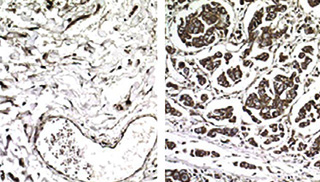

Cancer gone aggressive: In these samples from non-metastatic (left) and metastatic breast cancer (right), cells producing EXOSC2, a metastasis-promoting protein, are stained with a brown dye. The researchers found that EXOSC2 expression is enhanced in metastatic tumors because their cells have increased levels of a tRNA called GluUUC.

They found that the levels of two specific tRNAs were significantly higher in metastatic cells and metastatic tumors than in primary tumors that did not metastasize or healthy samples. “There are six different ways to encode for the protein building block arginine,” explains Tavazoie. “Yet only one of those—the tRNA that recognizes the codon CGG—was associated with increased metastasis.”

The tRNA that recognizes the codon GAA and encodes for a building block known as glutamic acid was also elevated in metastatic samples.

According to the researchers, two genes stood out among the list. Known as EXOSC2 and GRIPAP1, these genes were strongly and directly induced by elevated levels of the specific glutamic acid tRNA. “When we mutated the GAA codons to GAG— a “silent” mutation because they both spell out the protein building block glutamic acid—we found that increasing the amount of tRNA no longer increased protein levels,” explains Tavazoie. These proteins were found to drive breast cancer metastasis.